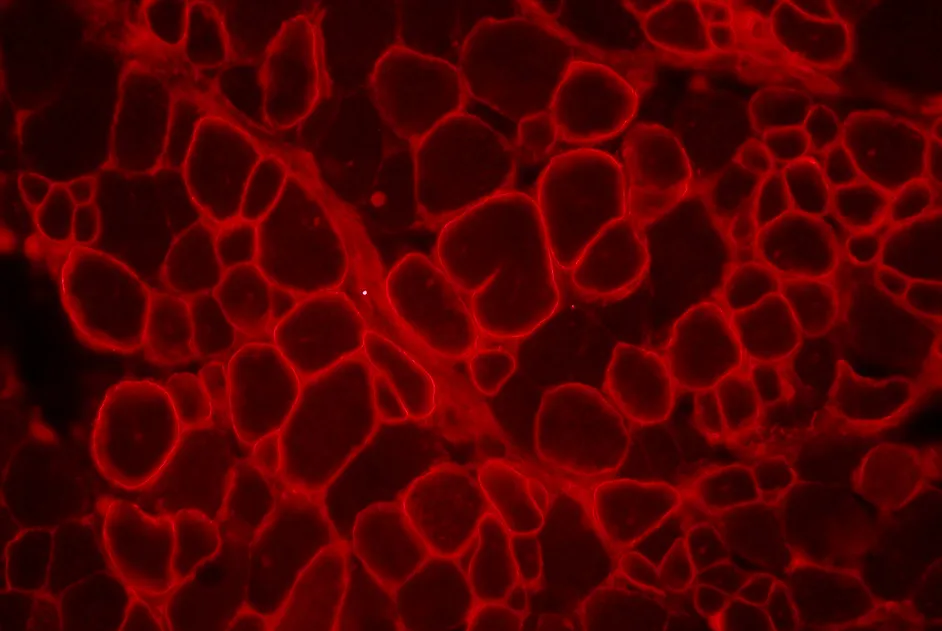

Premières études sur des fœtus FSH mettant en évidence l’expression de gènes impliqués dans la maladie dès ce stade précoce du développement.